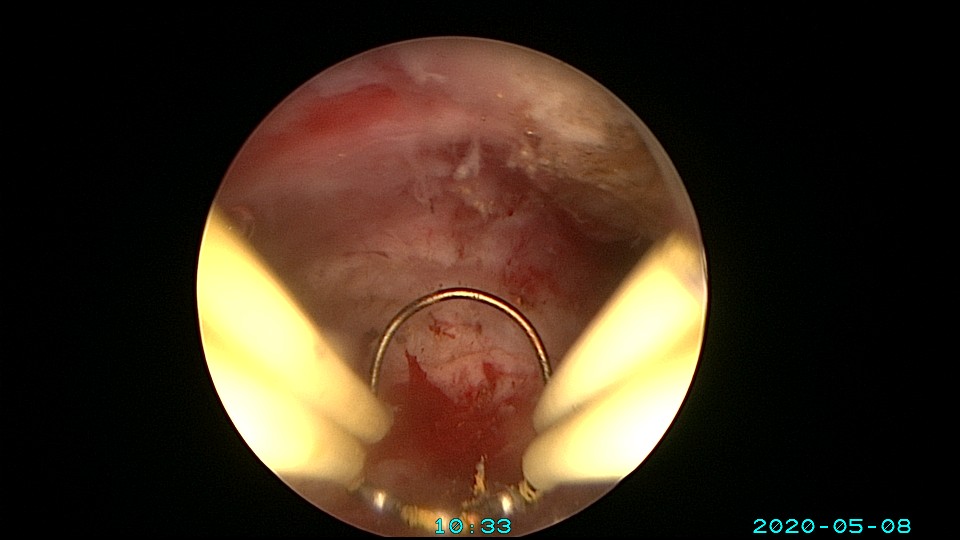

患者32岁,G10P1,剖宫产1次。2020年2月人流术后闭经2+月,2020年5月宫腔镜探查见剖宫产切口憩室,宫颈内口以上广泛封闭粘连,AFS评10分,双极电针分粘效果差,扩张宫颈管,改用双极电切分粘,恢复宫腔形态,显露双侧输卵管开口。2020年6月宫腔镜二探取球囊,宫腔形态正常,双侧输卵管开口可见。2020年10月自然妊娠,2021年2月初的某一天,在电梯里,病人的老公认出我是给他老婆做手术的医生,表达感谢之余,讲病人因先兆流产在产科保胎,情绪不稳定,甚至想终止妊娠,医生及家属努力安抚病人。2021年5月,36+3周剖宫产分娩。现37岁,G11P2。